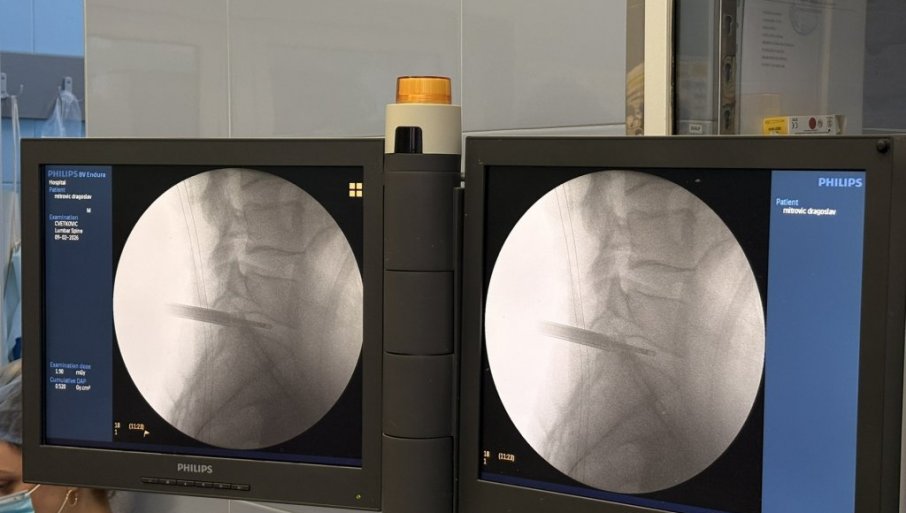

U UNIVERZITETSKOM kliničkom centru Vojvodine uspešno je izvedena prva kompletno endoskopska operacija lumbalne diskus hernije.

Operaciju su izveli doc. dr Bojan Jelača i prof. dr Đula Đilvesi, čime je UKCV napravio značajan iskorak u primeni savremenih minimalno invazivnih tehnika u spinalnoj hirurgiji. Pacijent koji je 8. februara operisan ovom metodom, otpušten je kući već narednog dana, uz uredan postoperativni tok i preporuku za dalji rehabilitacioni tretman.

Diskus hernija predstavlja jedno od najčešćih oboljenja savremenog doba, koje u velikoj meri pogađa radno aktivnu populaciju i dovodi do hroničnog bola, smanjenog kvaliteta života i čestih odsustava sa posla. Suština endoskopske tehnike zasniva se na radu kroz radni kanal prečnika oko 8 mm, uz konstantnu endoskopsku vizuelizaciju i irigaciju.